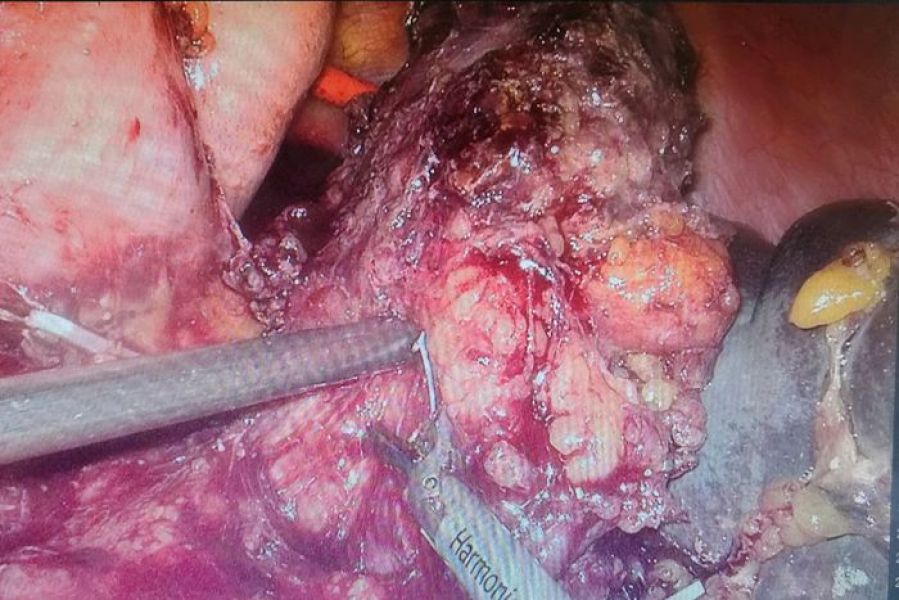

因患者高龄,且合并高血压,心肺功能差,为做到根治性手术,预计需联合多个脏器切除,淋巴结清扫,手术风险极大。选择手术方式有二:一是实施传统的开放手术,手术创伤大,术后恢复时间会更长,发生并发症风险加大;二是实施腹腔镜微创手术,可以大大减少患者的创伤应激,更符合加速康复(ERAS))的理念,使患者获得更大受益,但腹腔镜操作技术难度较开腹明显加大,对麻醉气腹要求更高,联合麻醉科反复讨论后决定,为患者实施3D腹腔镜下探查,胰腺体尾部联合脾脏切除手术。

经过充分的术前准备,手术于7月18日进行,由肝胆外科主任宋新主任医师台下指导,肝胆外科二病区手术团队遵循目前最先进的根治性顺行模块化胰脾切除术(RAMPS)术式,从显露到配合,从分离到缝合,到计划性的en-block标本完整切除,都是按照术前精心设计的步骤顺利操作,历时5小时,出血不足50ml,最后成功为患者实施了3D腹腔镜下胰体尾癌联合脾脏切除术,切除7、8、9、10、11、12b淋巴结及左肾前筋膜。术后病理报告提示:胰腺体尾部低分化腺癌,肿瘤切除标本切缘阴性,淋巴结无转移。术后继续将加速康复理念应用于该患者,术后第一天拔出胃管,鼓励患者床上活动,肺功能锻炼;术后第二天拔出导尿管,开始下床活动。一周后复查胰腺CT提示病灶已完整切除,无出血及胰瘘等并发症发生,患者康复出院,目前回访无异常。

据肝胆外科医生介绍,胰腺癌被称为“沉默的杀手”,体尾部癌更少见,恶性程度更高,侵袭性强,易突破胰腺被膜,侵犯左肾上腺,甚至突破肾筋膜进入肾脂肪囊,而且在常规体检中,医生看不到或感觉不到这种肿瘤。为了帮助诊断,只能通过腹部的影像学检查(如超声或CT扫描)来发现。为做到淋巴结及周围脂肪组织的彻底清扫,近年来主张实施先进的胰体尾癌根治性顺行模块化胰脾切除术(RAMPS),绝大多数医院一直采用开放的手术方式。随着对上腹部解剖认知的不断深入,凭借丰富的开腹经验,加上历年来积累的熟练的腹腔镜操作技术,肝胆外科医生已成功完成多例腹腔镜下复杂的肝胆胰手术,借助3D腹腔镜,使得术野立体感更强,显露更清晰,使得医生更加有信心挑战更多复杂的病例。